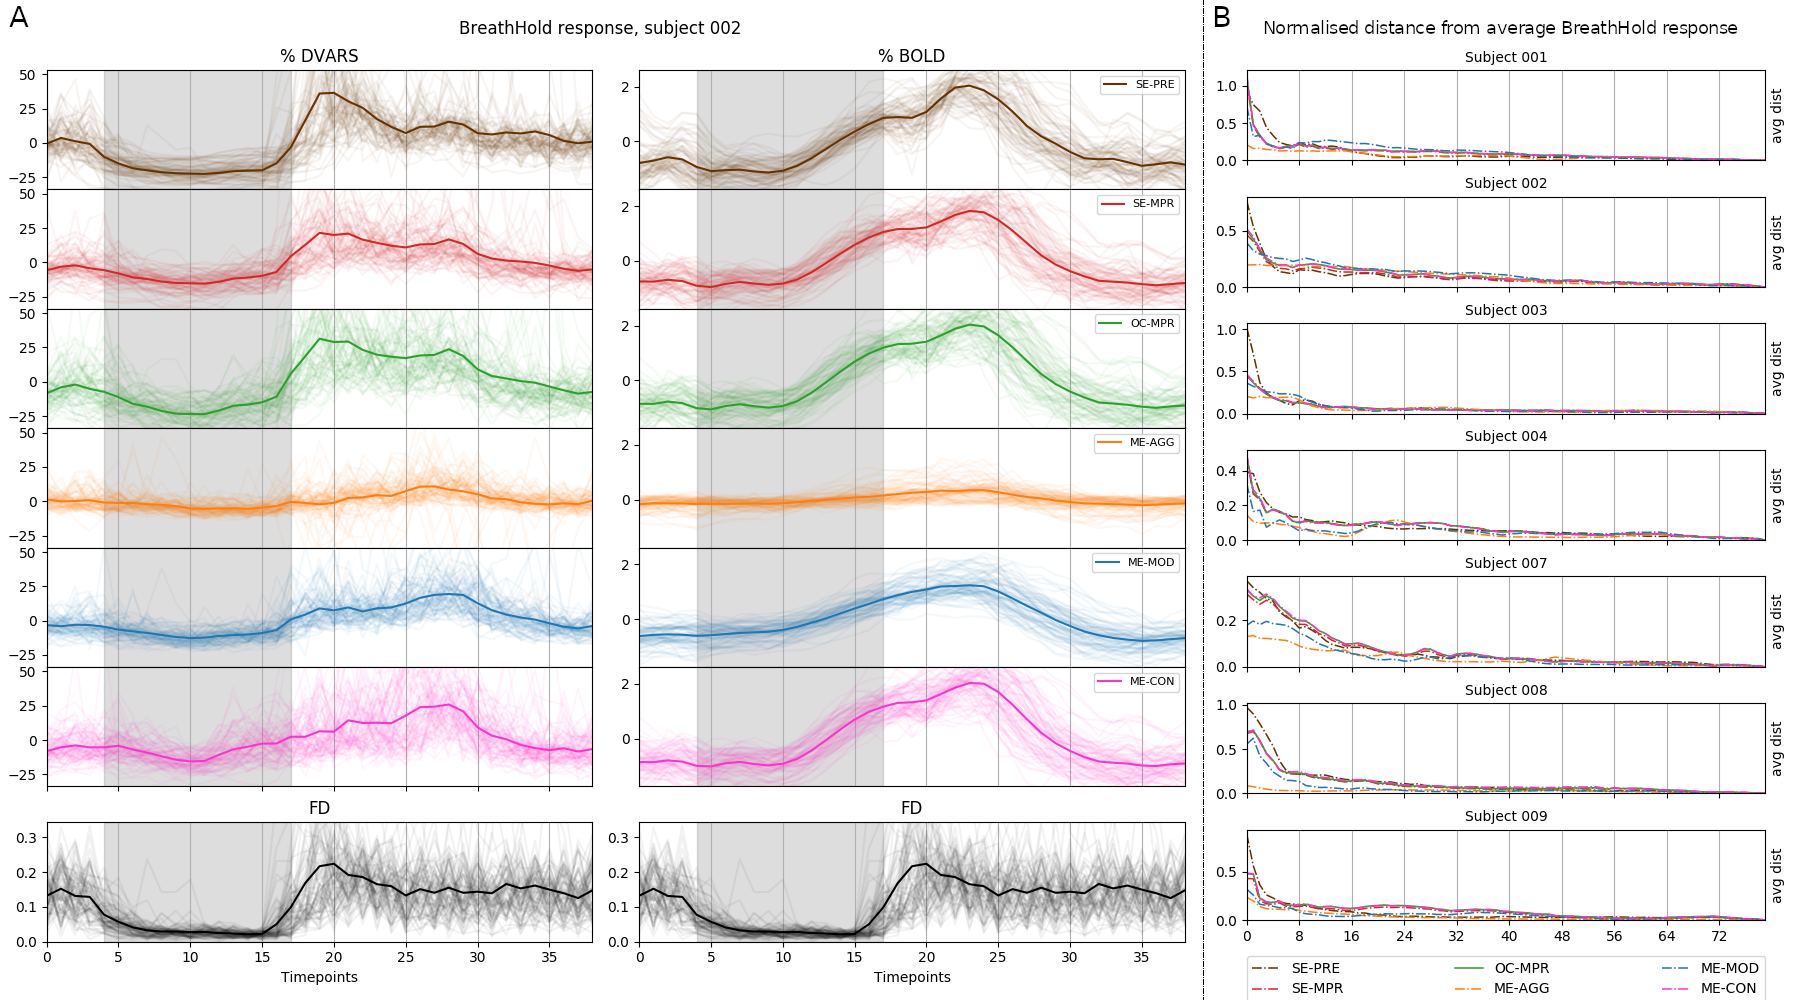

Alternative ICA based denoise (sequential)

Average % BOLD and DVARS across all trials

↑

↑

↓

↓

↓

↓

↓

Aggressive denoise removes signal of interest

OC and E-02 denoise affects the signal of interest more than ICA denoise